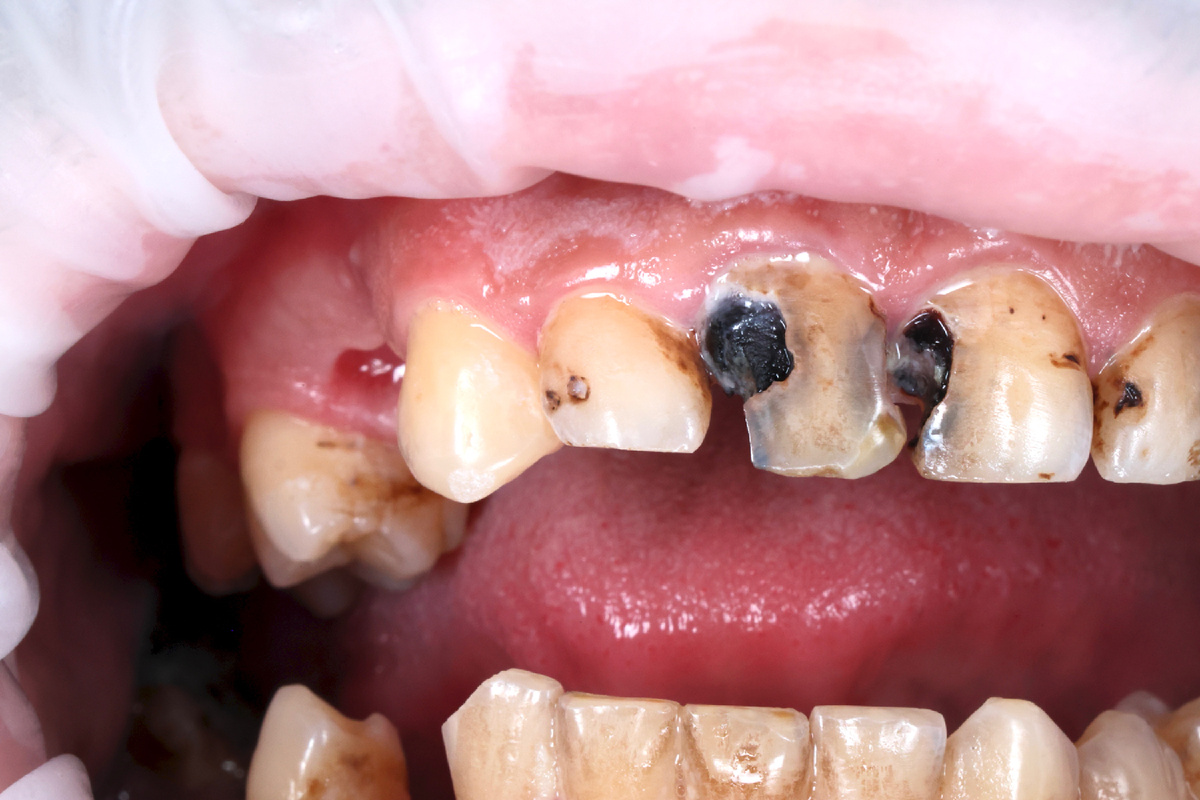

Состояние зубов до лечения